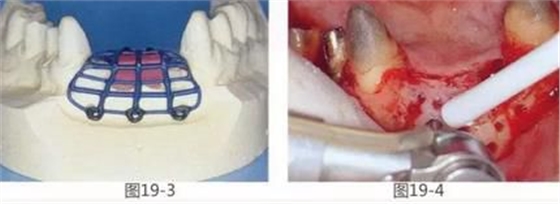

圖19-3 經(jīng)判斷,若在該病例中使用覆膜和骨移植材料并用的GBR法,就會使新生骨的形成量產(chǎn)生局限性。因此,使用了以黃金框架為支柱的GBR法,以防止覆膜脫落。事先進(jìn)行取模,用蠟片制作出預(yù)計(jì)的骨量和骨形態(tài),并在此基礎(chǔ)上進(jìn)行上蠟,鑄造黃金框架。

圖19-4 為了確保血液供給而進(jìn)行了皮質(zhì)剝除術(shù),這時通過OCT采集自體骨。